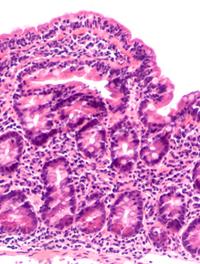

Une méta-analyse révèle que la transplantation de microbiote intestinal (TMI), également communément appelée transplantation de microbiote [...]